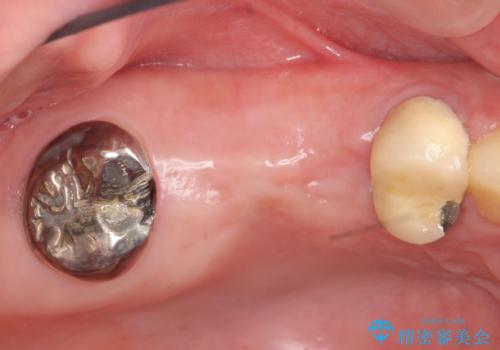

右上の567ブリッジを外したところ、右上5は歯根破折により保存不可能だったため、右上56部にインプラントを埋入し欠損補綴を行いました。

また右上5部に関しては抜歯時に歯槽堤保存術(抜歯窩に人工骨の填入を行う手術)を行い、骨の欠損を最小限に止めています。